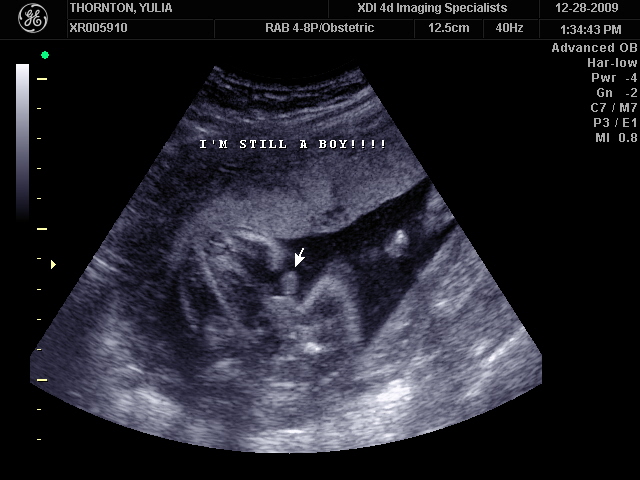

Ну ладно, тогда и я нашего писюна покажу  Надеюсь, Джеффри на меня не обидится Вот это в 23 недели: (там оборудование переключалось из режима 3Д в обычный 2Д)

А это в 30 недель